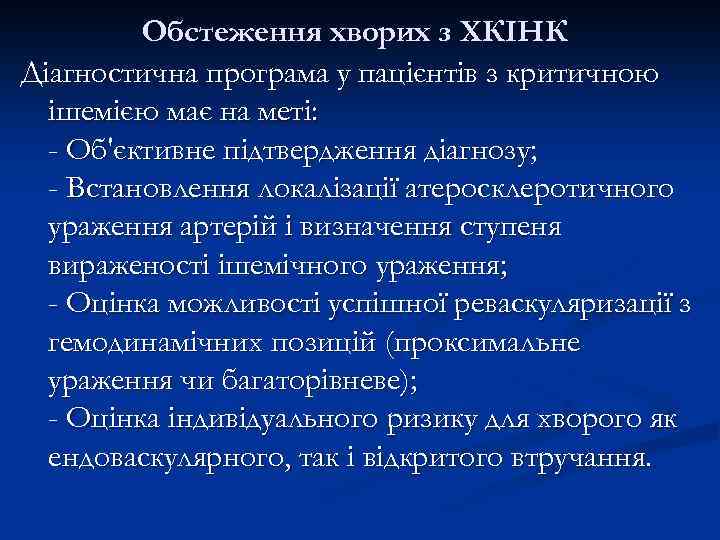

Обстеження хворих з ХКІНК Діагностична програма у пацієнтів з критичною ішемією має на меті: - Об'єктивне підтвердження діагнозу; - Встановлення локалізації атеросклеротичного ураження артерій і визначення ступеня вираженості ішемічного ураження; - Оцінка можливості успішної реваскуляризації з гемодинамічних позицій (проксимальне ураження чи багаторівневе); - Оцінка індивідуального ризику для хворого як ендоваскулярного, так і відкритого втручання.

Обстеження хворих з ХКІНК Діагностична програма у пацієнтів з критичною ішемією має на меті: - Об'єктивне підтвердження діагнозу; - Встановлення локалізації атеросклеротичного ураження артерій і визначення ступеня вираженості ішемічного ураження; - Оцінка можливості успішної реваскуляризації з гемодинамічних позицій (проксимальне ураження чи багаторівневе); - Оцінка індивідуального ризику для хворого як ендоваскулярного, так і відкритого втручання.